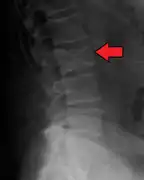

The diagnostic examination of a person with suspected multiple myeloma typically includes a skeletal survey. This is a series of X-rays of the skull, axial skeleton, and proximal long bones. Myeloma activity sometimes appears as "lytic lesions" (with local disappearance of normal bone due to resorption) or as "punched-out lesions" on the skull X-ray ("raindrop skull"). Lesions may also be sclerotic, which is seen as radiodense.[64] Overall, the radiodensity of myeloma is between −30 and 120 Hounsfield units (HU).[65] Magnetic resonance imaging is more sensitive than simple X-rays in the detection of lytic lesions, and may supersede a skeletal survey, especially when vertebral disease is suspected. Occasionally, a CT scan is performed to measure the size of soft-tissue plasmacytomas. Bone scans are typically not of any additional value in the workup of people with myeloma (no new bone formation; lytic lesions not well visualized on bone scan).

Pathological fracture of the lumbar spine due to multiple myeloma